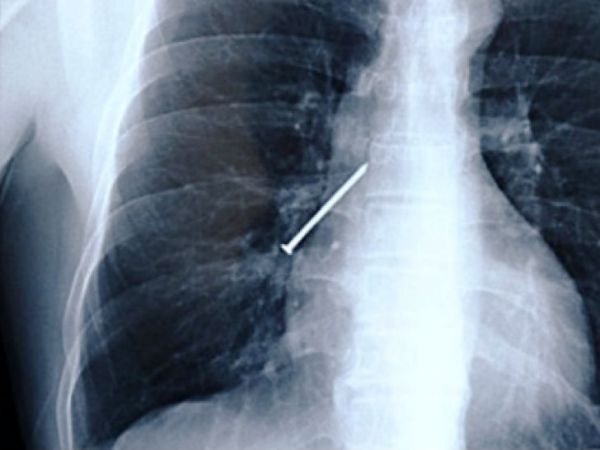

Вы когда-нибудь держали в зубах гвоздь, когда руки заняты молотком? Вот вам снимок мужчины из Китая, который во время работы закашлялся.

Мы вас предупреждали, не смотрите, если вы только что сели обедать.